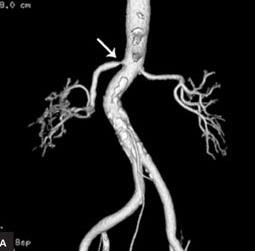

CT 검사에서 오른쪽 신장이 작아져 있고 그쪽으로 가는 동맥이 좁아져 있는 것이 관찰된다.그런데 고혈압 중 신장 때문에 2차적으로 혈압이 오르는 병이 있다. 즉 위 사진처럼 신장에 가느다란 동맥이 좁아져 생기는 고혈압을 말한다. 이런 병은 전체 고혈압의 5% 정도로 많다는 연구 결과도 있다. 이를 신장혈관성고혈압(renovascular hypertension)이라고 한다.

이 병은 30세 이전에 고혈압이 생기는 분에게 잘 보이는데 이럴 경우 아직 정확한 원인은 알 수 없지만 신장, 혈관 벽에 섬유질, 근육층이 두꺼워져 생길 수 있다. 고혈압이 급격히 악화되는 악성 고혈압을 보이기 쉽고 ACE 억제제나 ARB 같은 혈압 강하제를 사용하면 renin-angiotension-aldosterone system에 작용해 신장 기능이 더욱 악화된다. 50세 이상 갑자기 고혈압이 발생하면 신장동맥의 동맥경화로 인한 신장혈관성 고혈압을 의심해 볼 수 있다.증상이 없더라도 양쪽 신장의 크기 차이가 있고 달리 설명할 수 없는 신장 기능 저하가 있다면 이 병을 고려해야 한다. 또 설명할 수 없는 폐울혈이 생겨도 이 병을 한번쯤 의심해야 한다.

위 사진처럼 신장으로 가는 동맥이 7585%가 막혀야 고혈압이 생기고 60%까지는 증상이 없다. 만일 이 질환이 빨리 발견되면 이 혈관을 수술로 확장시켜 완쾌할 수도 있기 때문에 중요한 병이다.